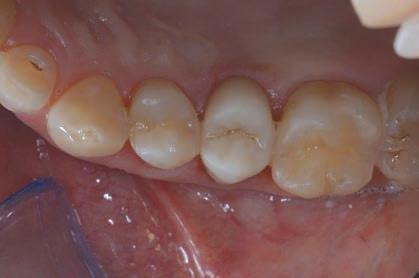

Figure 20: Application of the silane coupling agent to be left in place for at least 60” Figure 21: Adhesive cementation with adhesive composite resin. The absence of bleeding, the respect of the manufacturer’s instructions and the control of the prosthetic margins during the procedures is fundamental for the maintenance and the good outcome of the cementation. Figure 22: Final palatal view. Note the excellent integration of the margins also on the palatal side.

At the end of the procedures, the restoration was precisely seated at equigingival level of the margins, it appeared to be morphologically integrated in the dental arch, with correct contact points and with a good chromatic match with the adjacent elements (Figs. 21-24). Upon X-ray examination, it was possible to see that the subgingival margins were also integrated, without any step or any plaque-retaining area that could be a problem for the home dental hygiene (Fig. 25). The patient didn’t refer pain anymore and was completely satisfied with the prosthetic rehabilitation, that she found perfectly integrated at both functional and chromatic levels. She also found the colour of the prosthesis was better than her natural teeth.